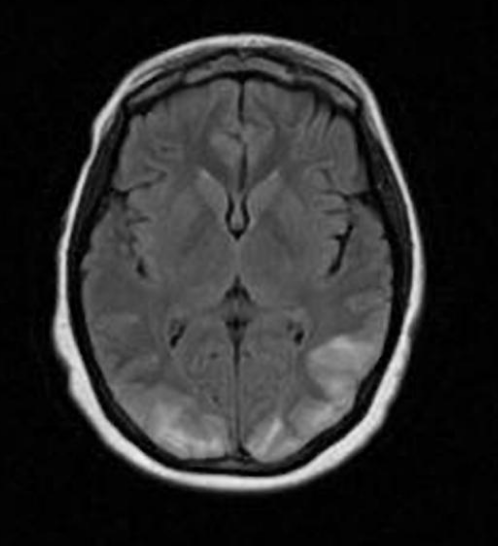

Estudo de imagem para excluir isquemia ou hemorragias

- pode haver atrofia cerebral ou (especialmente em DM) aumento do sinal nas regiões corticais e subcorticais em regiões frontal, parietal e occipital ==> edema localizado

- PRES ou hipersinal bilateral em T2/FLAIR em gânglios da base